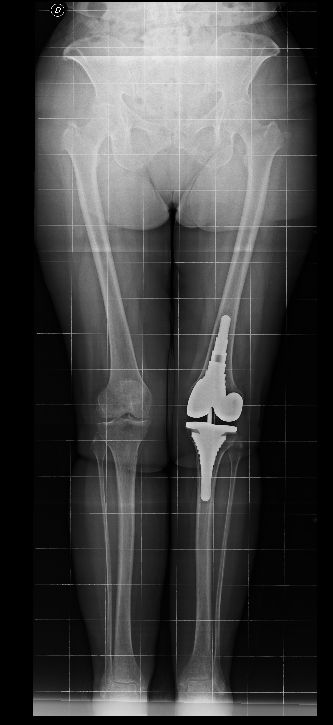

Da quando ha preso servizio presso l’Ospedale del Delta si è sempre occupato della chirurgia protesica del ginocchio sia monocompartimentale che totale acquisendo esperienza anche sulle tecniche basate sulla navigazione assistita che sull’impianto di protesi custom-made. Di routine esegue interventi di chirurgia artroscopica per il trattamento delle patologie meniscali e cartilaginee e di ricostruzione del legamento crociato anteriore mediante varie tecniche